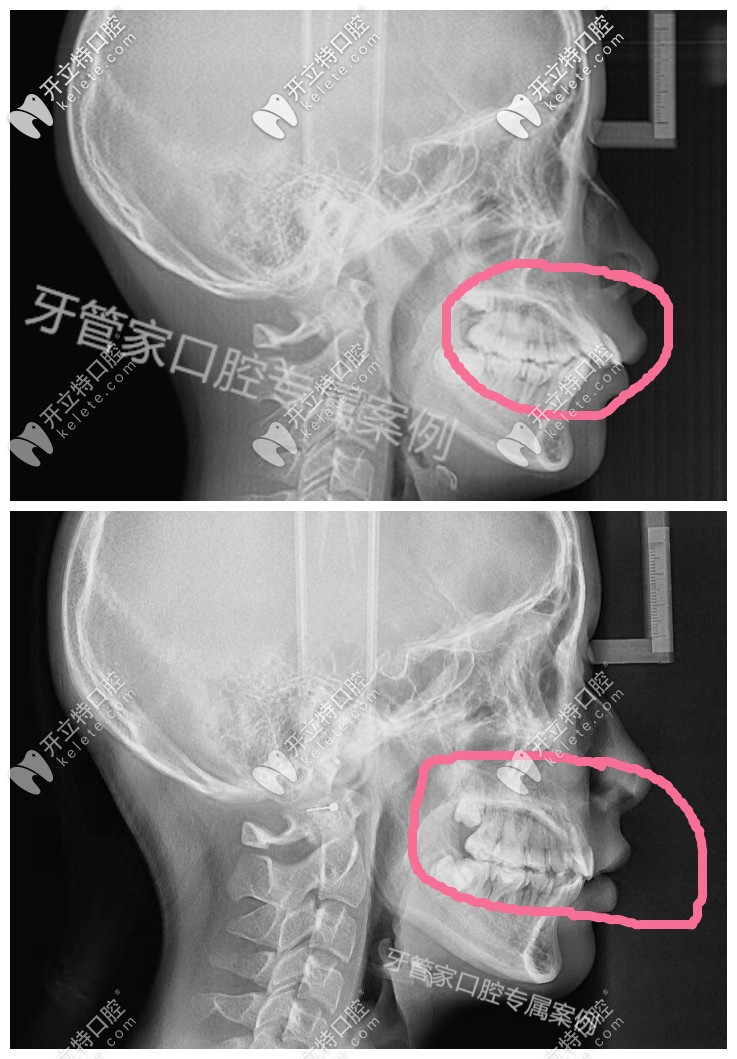

1.拍X光片,檢查牙齒數(shù)目和牙根情況。